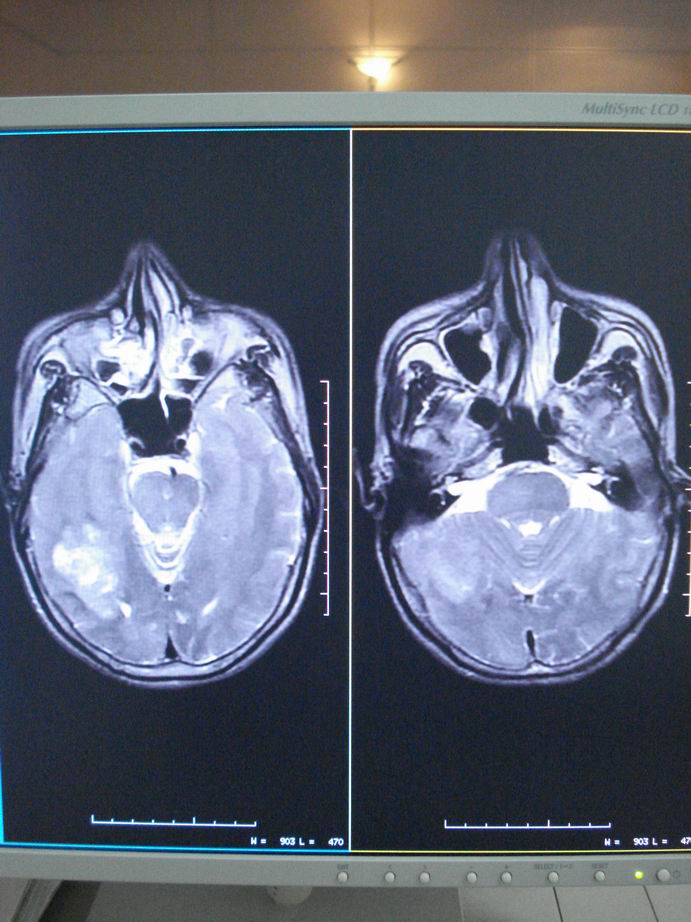

男60岁,左侧肢体乏力及精神异常10天,血压正常,血常规,肝肾功正常,腰穿无异常,请教颅内多发病灶,考虑什么?感染?肿瘤(转移性?)还是其它?

脑内多发占位性病变,首先考虑感染性病变,其次是转移瘤。

结合病人高龄,考虑转移瘤